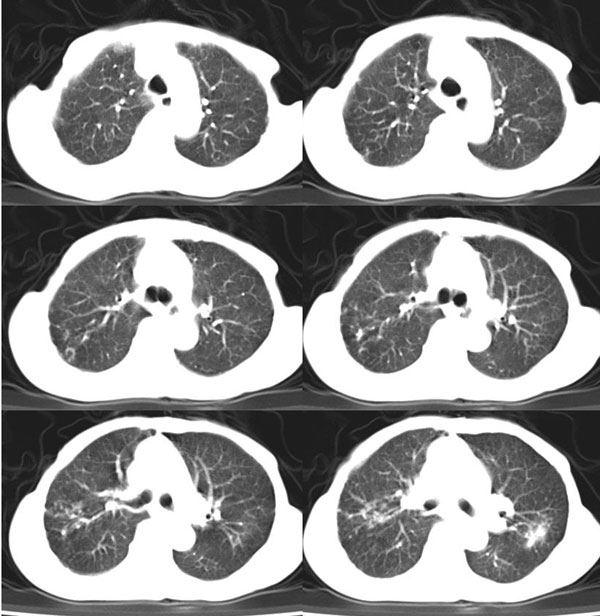

女:73岁;因一月前感冒后咳嗽,发烧,有大量脓痰,并且有恶臭味。

5毫米局部薄平扫

肺窗

右肺下叶肺脓肿

补充_____伴双肺血行播散

右肺下叶示片状致密影密度不均,内见一空洞有宽液平,并可见壁结节周围示散在斑片模糊影,左下肺亦见一斑片模糊影,考虑 肺脓疡,肺癌不除外。

发烧,有大量脓痰,并且有恶臭味,空洞,大液平,比较典型的肺脓疡